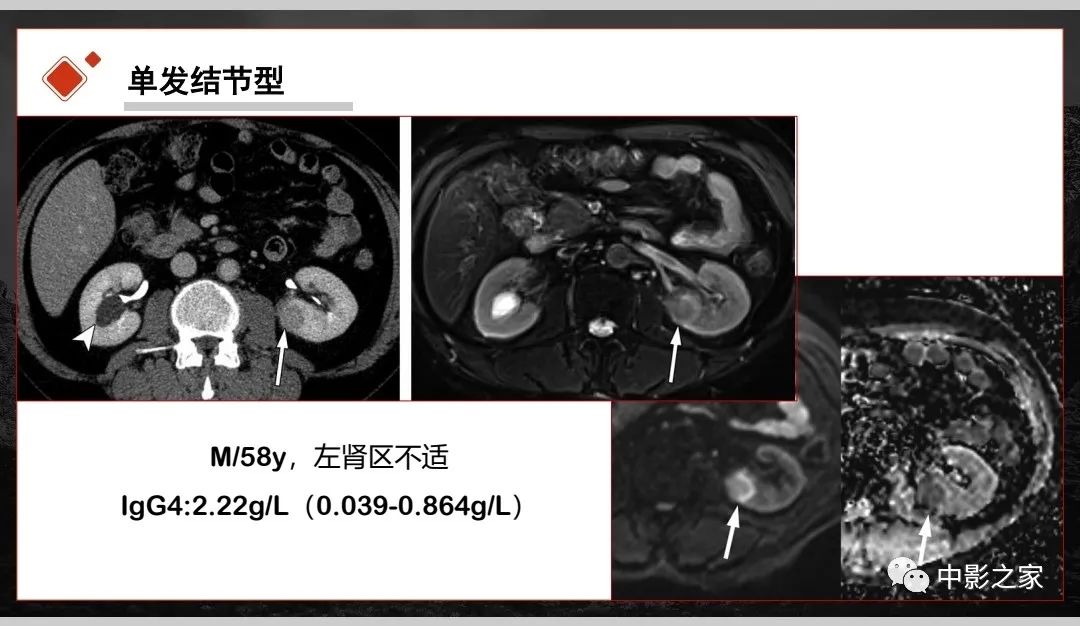

肾脏IgG4-RD临床、病理及影像特征